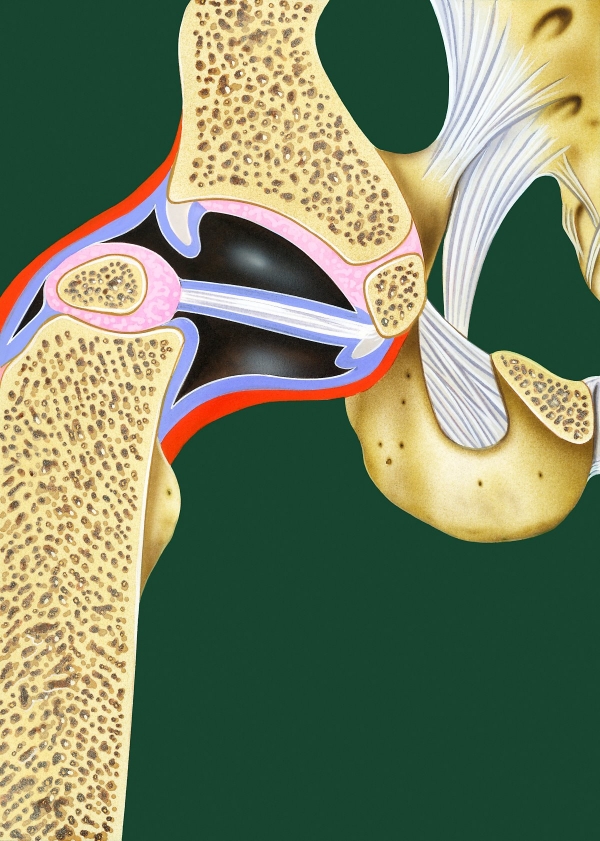

고관절 통증 증상(엉덩관절)은 오른쪽과 왼쪽의 골반과 넙다리뼈가 연결된 관절의 통증을 일컫습니다. 고관절은 상체의 하중을 분산시키는 역할을 하며, 일어서거나 앉거나 일상생활에서 자주 쓰이는 관절이며 부담도 잘 받게 됩니다. 모양도 크기도 탁구공만 합니다. 일상적으로 걸을 때 고관절에 체중의 3~4.5배의 무게가 실리게 됩니다. 계단을 오를 때는 대퇴골두에 전해지는 무게는 몸무게의 8배, 달리는 경우 10배에 가까운 하중을 견뎌내애 한다고 합니다. 탁구공 크기만 한 대퇴골두가 감당하기에는 너무 무겁기 때문에 고관절이 느끼는 부담도 크고 쉽게 손상될 수 있습니다. 다른 관절과 마찬가지로 감당하기 어려운 충격이나 무게가 가해지면 고관절 통증 증상이 발생하게 되는데요. 퇴행성 고관절염, 대퇴골 골절, 대퇴골두 무혈성 괴사, 선천성 고관절 탈구 등이 대표적인 고관절 통증 질환입니다.

노화로 연골이 마모되면서 생기는 골관절염은 골절과 같은 관절 외상으로 발생될 수 있으며, 감염성 관절염으로 발생되기도 합니다. 이러한 골관절염은 고관절 통증 증상 원인이 되기도 합니다.